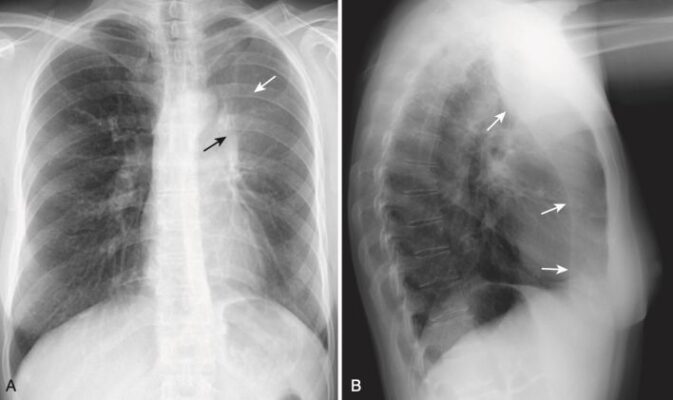

Xẹp phổi thùy giữa bên phải (xem Hình 1)

- Trên X quang thẳng:

- Có một đậm độ hình tam giác với đáy phủ bóng bờ với bờ tim phải và đỉnh của nó hướng về thành ngực bên.

- Rãnh liên thùy bé bị dịch chuyển xuống dưới.

- Trên phim X quang nghiêng:

- Có đậm độ hình tam giác với đáy hướng ra phía trước và đỉnh ở rốn phổi.

- Rãnh liên thùy bé có thể bị dịch chuyển xuống dưới và rãnh liên thùy lớn lên trên.